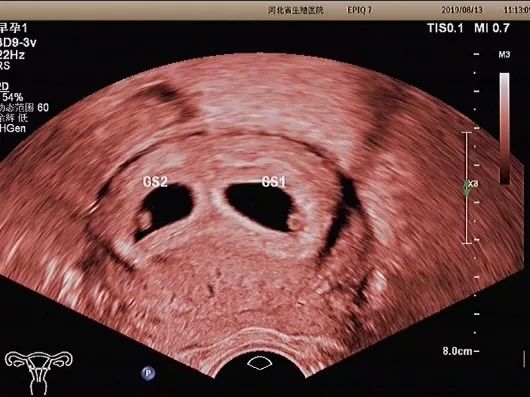

妊娠囊

确定妊娠囊是否在宫腔内,妊娠囊在宫腔内的位置、数目及大小。妊娠囊的大小可随孕周增长而增长。

优势一

经阴道超声检查发现

妊娠囊、卵黄囊的时间

早于经腹部超声

常能发现经腹部超声

不能发现的宫内早早孕和异位妊娠